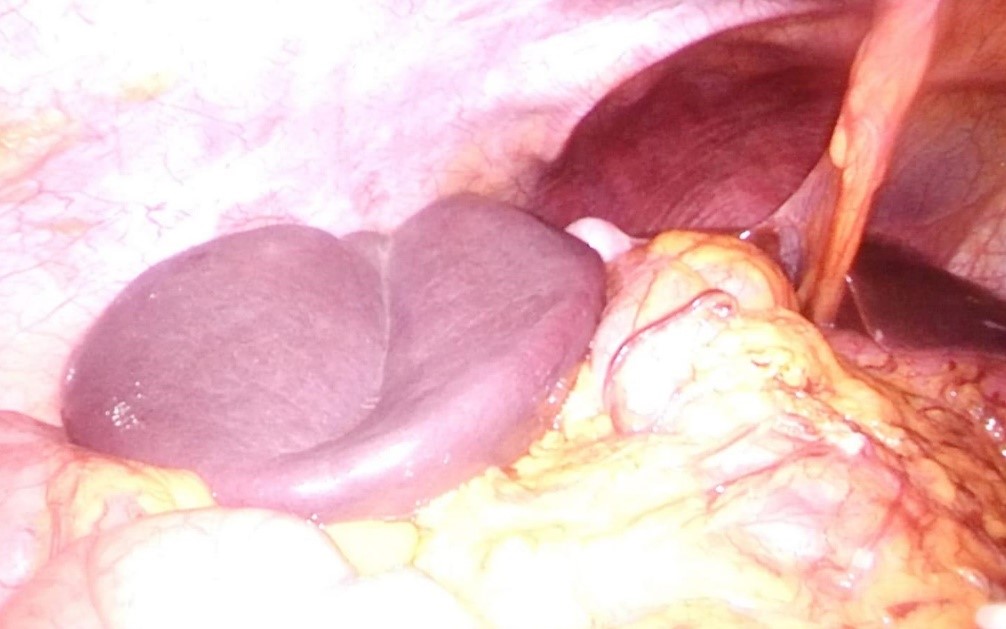

Se programó la cirugía para realizar esplenopexia laparoscópica (LPS). Durante la cirugía, el bazo se encontraba en posición subhepática, sin apreciarse líquido libre ni otras alteraciones (ver imagen 2). Debido a un sangrado intraoperatorio durante la pexia a nivel de la vena esplénica que no se pudo controlar, finalmente se efectuó una esplenectomía, seccionándose el hilio esplénico con endograpadora. El bazo se extrajo en una bolsa de LPS, finalizando la cirugía sin otras complicaciones.

Figura 2: Posición suprahepática del bazo durante el procedimiento quirúrgico: esplenectomía LPS.